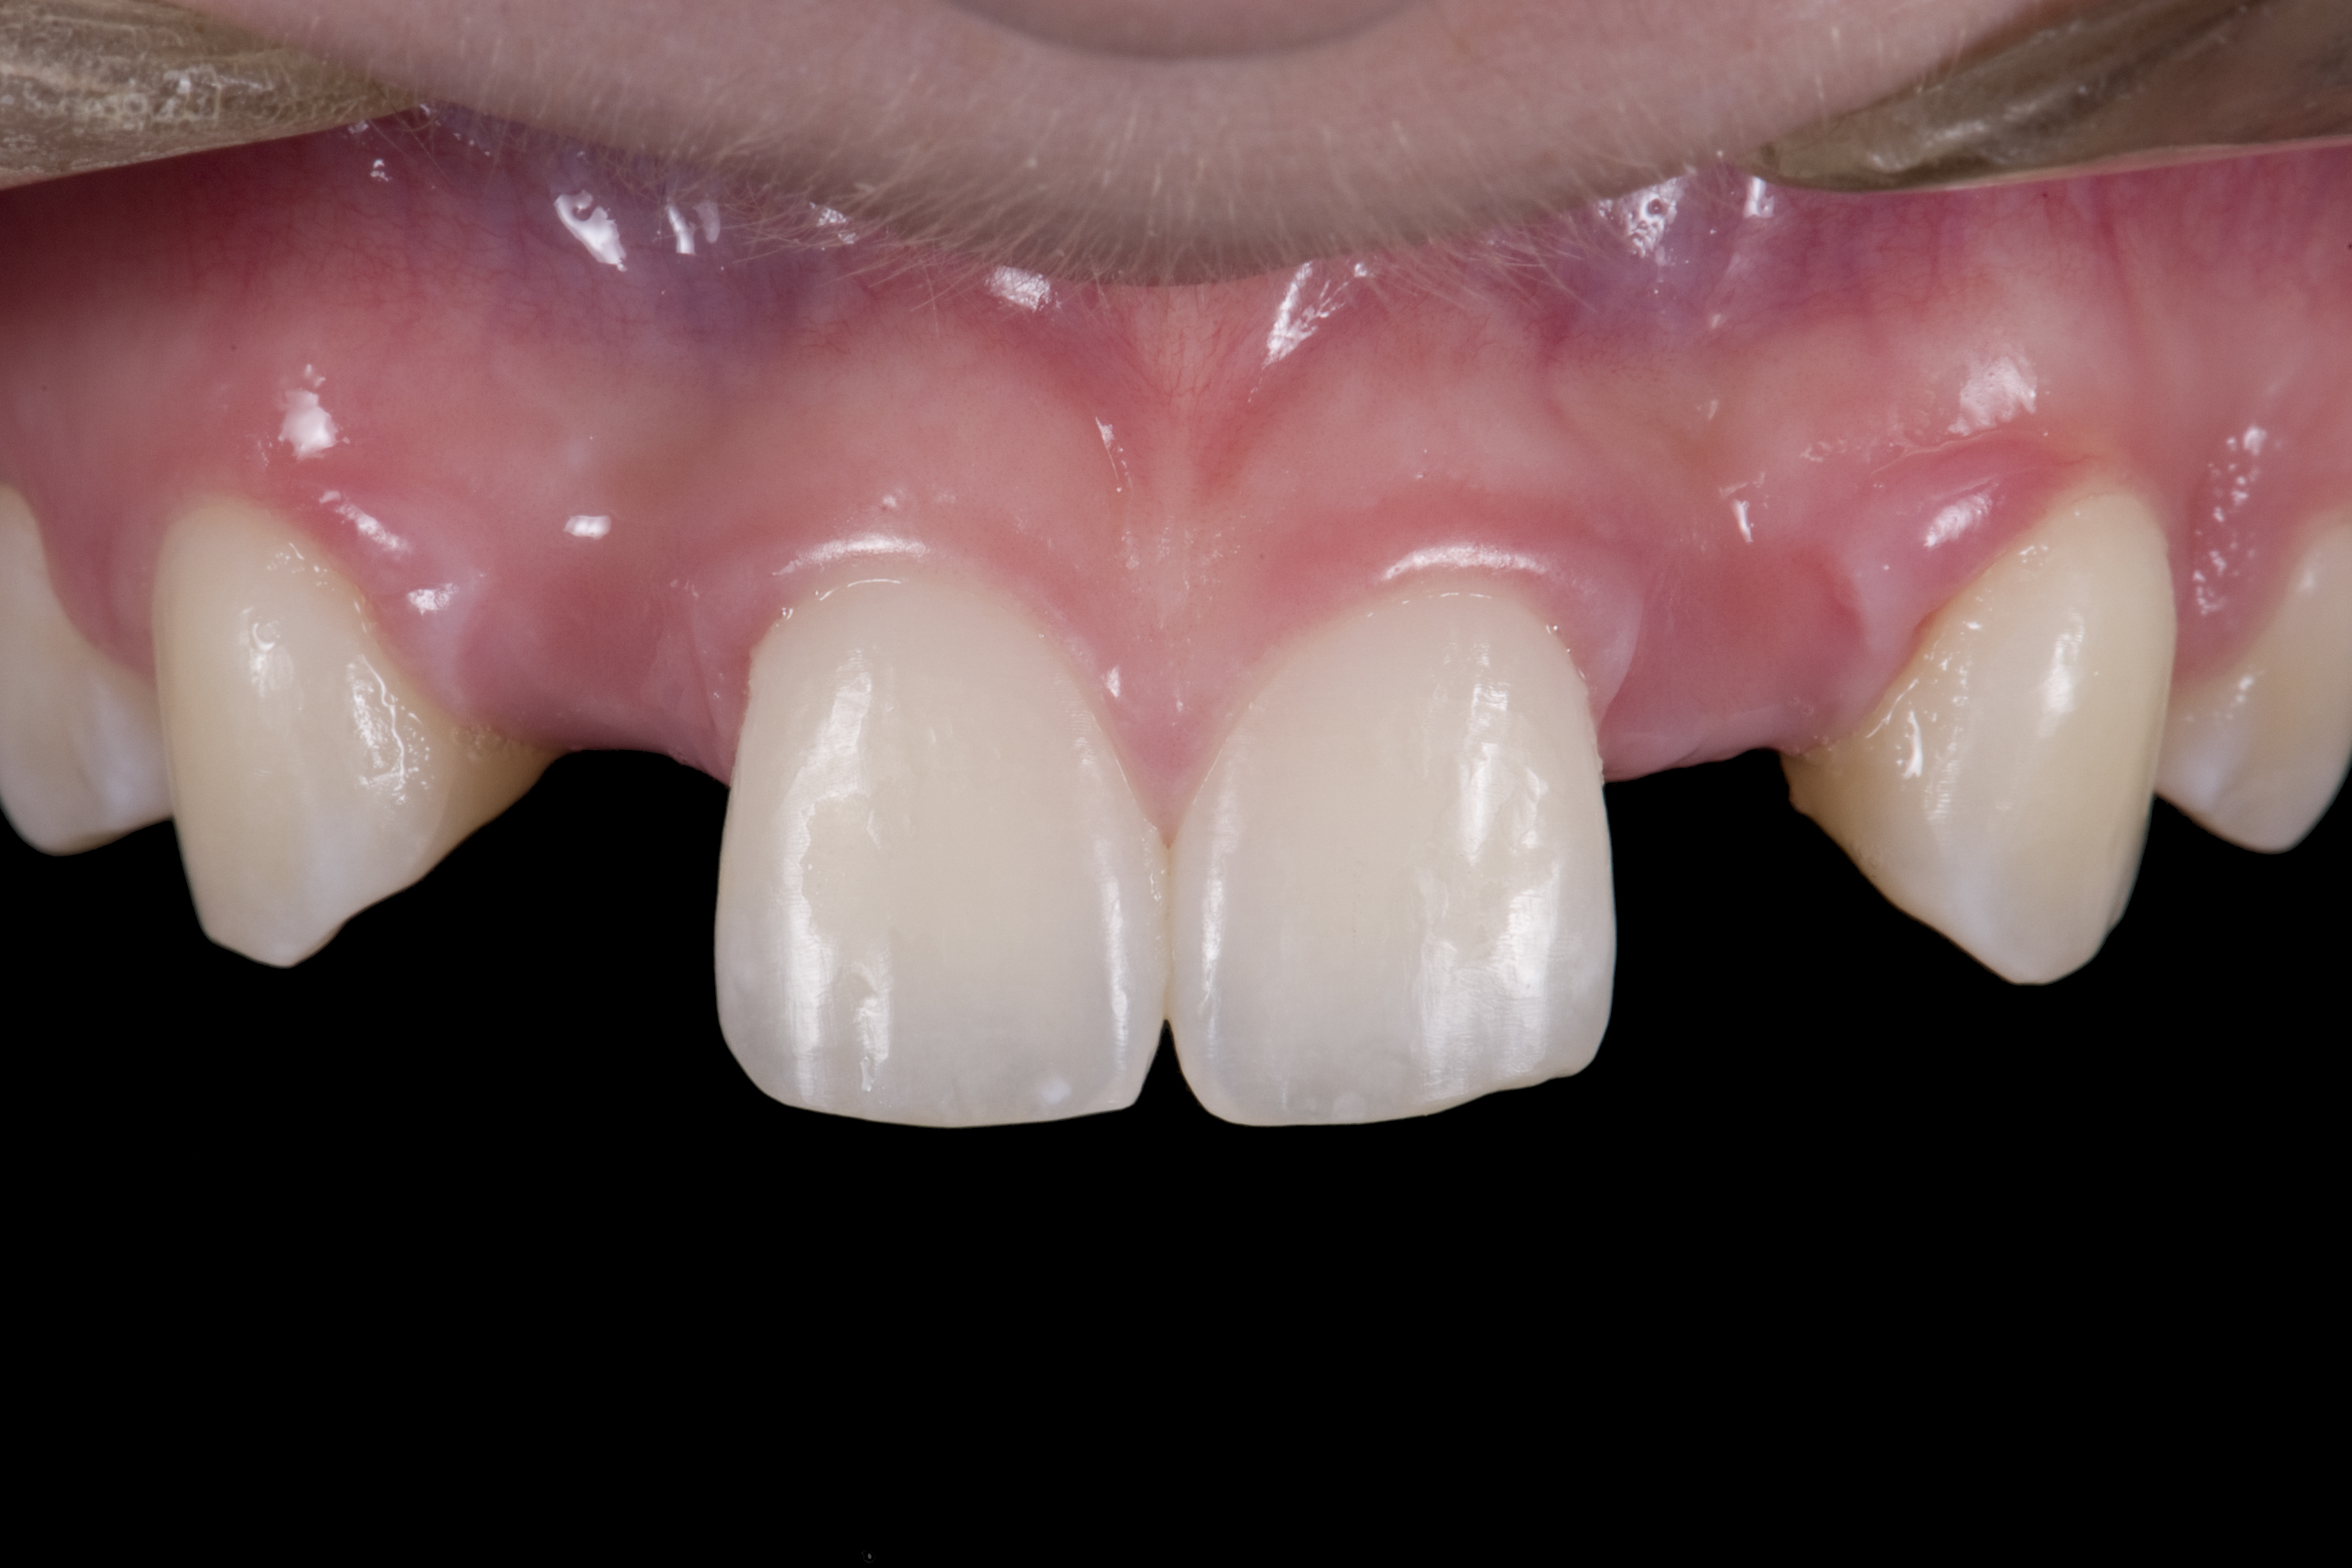

(1.) Initial presentation. Note midline shift to right, missing right lateral incisor, and diminutive left lateral incisor in crossbite.

Figure 1

(2.) After orthodontic alignment of teeth and bleaching. Note alveolar deficiency in right lateral incisor site and diminutive left lateral incisor.

Figure 2

A 14-year-old patient presented to the office with his mother (Figure 1). His chief complaint involved the large spaces between the teeth created by his missing right maxillary lateral incisor and his small left maxillary lateral incisor. He desired to replace the missing tooth with an implant and create a beautiful smile. Upon examination, he was found to have a class I canine and molar relationship, but because he had a tooth size/arch size discrepancy and space distal to the right central incisor, the remaining incisors had drifted to the right. The left maxillary lateral incisor was peg-shaped and in a cross bite position. Studies have shown a clear association between congenitally missing teeth and reduced tooth size.59-62 Because he was only 14-years-old at the time and could not have implants placed until the cessation of growth (somewhere in the vicinity of 22 years old), he was sent to the orthodontist for alignment of the teeth.16,17 After 2 years of orthodontics, the appliances were removed, and his tooth coloration was improved using carbamide peroxide bleaching (Figure 2). Because some form of provisional needed to be placed until he was finished growing, a double-wing metal resin-bonded bridge was chosen. As discussed earlier, this is the ideal transitional prosthesis for patients that have congenitally missing maxillary lateral incisors. The benefits of this type of prosthesis include its ability to be removed and rebonded during the surgical phase of treatment and its ability to retain the roots in their proper position after orthodontic treatment.16 The final plan for the patient was to increase the width of the central and the maxillary left lateral incisor, utilizing porcelain laminate veneers to achieve the appropriate width/length ratio of 80%. A wax-up was created to idealize tooth size, a putty matrix was made from the wax-up to facilitate bonding of the incisors, and a non-precious, double-wing metal resin-bonded bridge was fabricated for lateral incisor replacement. Once the teeth were bonded to ideal size, the “Maryland Bridge” was fabricated from a polyvinyl arch impression with the newly bonded teeth (Figure 3). The metal frame was cast from a non-precious alloy to allow for fabrication of a very thin frame and to create a better surface for bonding. After sandblasting the internal aspect of the frame with CoJet™ silica (3M ESPE), accomplishing salinization, and executing cementation with a dual-cure resin cement, a fairly good adhesion to the frame was anticipated.29 The enamel surface was etched with phosphoric acid for 30 seconds, the primer (Single Bond Plus, 3M ESPE) was applied to both the internal surface of the sandblasted framework and the etched enamel, and the bridge was cemented with RelyX™ ARC (3M Espe) dual-cured resin cement (Figure 4 and Figure 5).